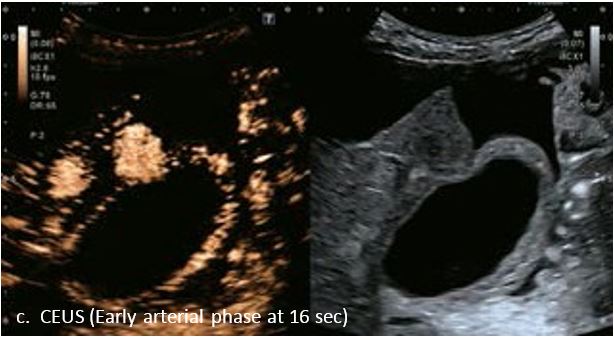

Оцінка результатів лікування ГЦК

Проведено повторне обстеження 79-річного чоловіка з цирозом печінки В, ускладненим ГЦК, після транс-артеріальної хіміоемболізації (ТАХЕ). Було виявлено нове ураження, розташоване поруч з ураженням після ТАХЕ. На сірошкальному зображенні чітко видно нове ураження, але складно виявити рецидив ГЦК в зоні ураження після ТАХЕ. За допомогою кольорового картування SMI (cSMI) можна побачити розвинену судинну мережу всередині нового вогнища ураження. Для оцінки результату лікування було виконано CEUS. За допомогою CEUS можна легко дослідити як нове ураження, так і рецидив ГЦК у вогнищі ураження після TACE. Нове ураження демонструє гіперпосилення артеріальної фази і відсутність вимивання до 5 хвилин, отже, це ураження LI-RADS 4, ймовірна ГЦК за критеріями LI-RADS. Підживлюючі судини можна чітко спостерігати в ранній артеріальній фазі. Для ураження після TACE, більша його частина не підсилюється, однак, в артеріальній фазі спостерігається ділянка гіперпосилення у верхній частині лікованого ураження, що вказує на рецидив ГЦК.

Малюнок 10